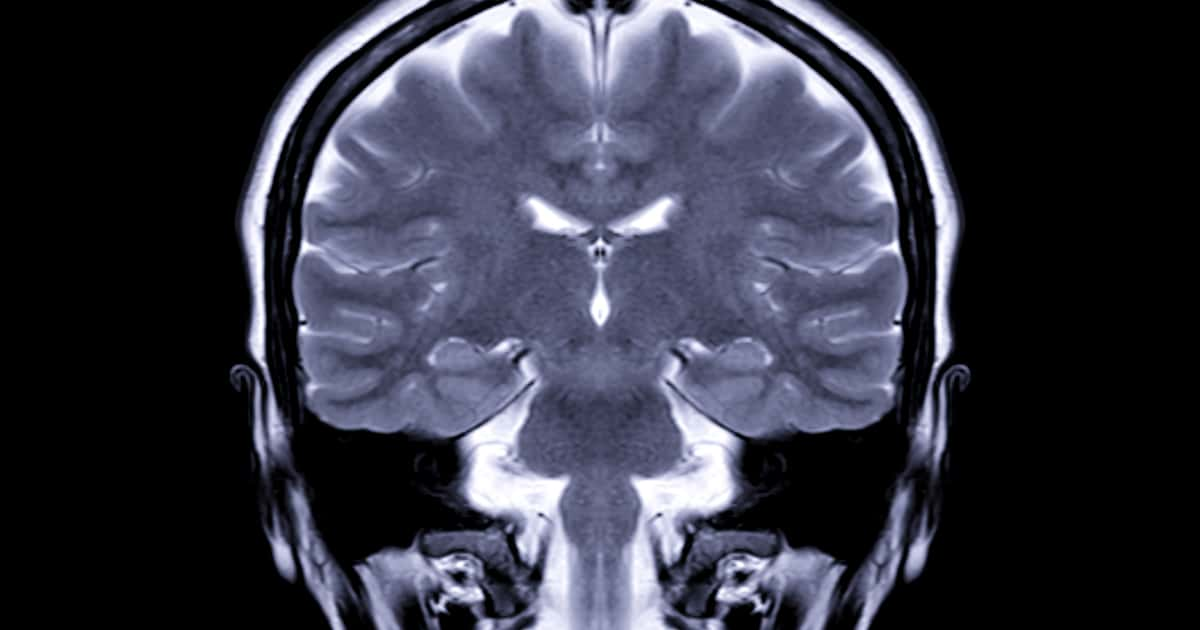

Combinando ressonância magnética e inteligência artificial, os cientistas identificaram que o álcool pode antecipar danos neurais que normalmente só apareceriam décadas depois, levantando um sinal de alerta especialmente para jovens que iniciaram o hábito ainda na adolescência.

A pesquisa avaliou 58 adultos com idades entre 22 e 40 anos, a maioria com histórico de consumo alcoólico desde a juventude. Após responderem a questionários sobre hábitos de bebida, os participantes foram submetidos a testes de flexibilidade cognitiva e exames de ressonância magnética em 3D.

A partir das imagens cerebrais, algoritmos de machine learning calcularam a chamada Diferença de Idade Predita (DAP), uma métrica que estima o quanto o cérebro aparenta ser mais velho do que a idade real da pessoa. Quanto maior o consumo de álcool, maior foi a discrepância — ou seja, maior o envelhecimento cerebral.